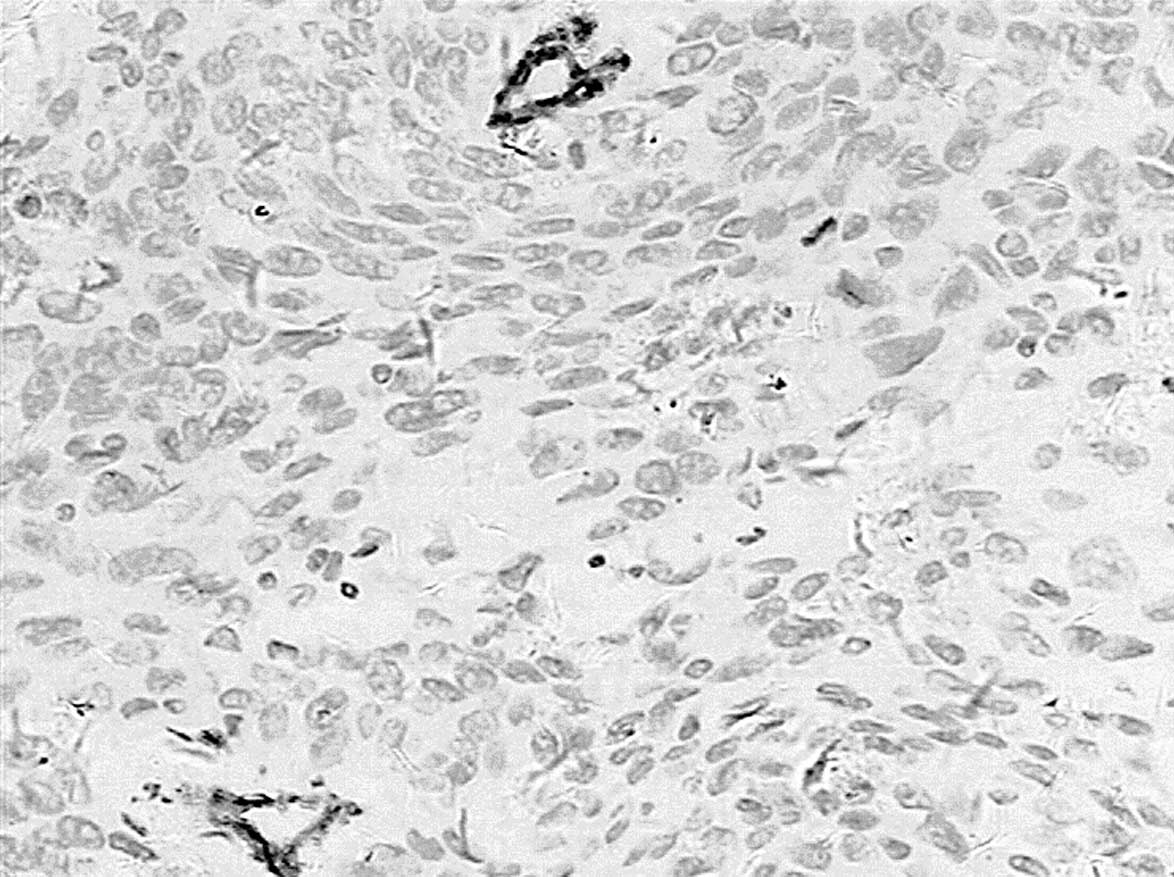

Correlation of CD146 expression and clinicopathological characteristics in esophageal squamous cell carcinoma

CD146, a cell adhesion molecule, is found in normal and tumor tissues. The level of its expression has been found to directly correlate with tumor progression and metastatic potential. The objective of this study was to investigate the expression of CD146 in esophageal squamous cell carcinoma (ESCC) and its correlation with clinicopathological parameters. Tumor specimens were collected from 63 patients with ESCC who underwent complete resection. We analyzed the CD146 expression levels in ESCC by immunohistochemistry. The expression of CD146 was detected and it was observed to correlate with clinicopathological parameters. Sixty‑three cases of normal squamous mucosa were included for comparison. CD146 expression was identified in 46.0% (29/63) of the ESCC samples, and no positive (weak to moderate or moderate to strong) expression was found in the normal squamous epithelium samples (χ2=27.248; P<0.0001). CD146 expression was associated with lymph node metastasis (χ2=5.117; P=0.024) and advanced clinical stage (χ2=4.661; P=0.031). CD146 expression was one of the significant predictors of survival (hazard ratio, 2.838; 95% confidence interval 1.102‑7.305). The overexpression of the CD146 gene was one of the important phenotypes and characteristics in ESCC carcinomatous change. We found that CD146 expression was associated with lymph node metastasis and advanced clinical stage, and was an indicator of poor prognosis in ESCC patients. CD146 may prove to be an important tumor marker for the individualized treatment for ESCC.

View Figures

Figure 1

Figure 2

Figure 3

Figure 4

Figure 5

Figure 6

Figure 7